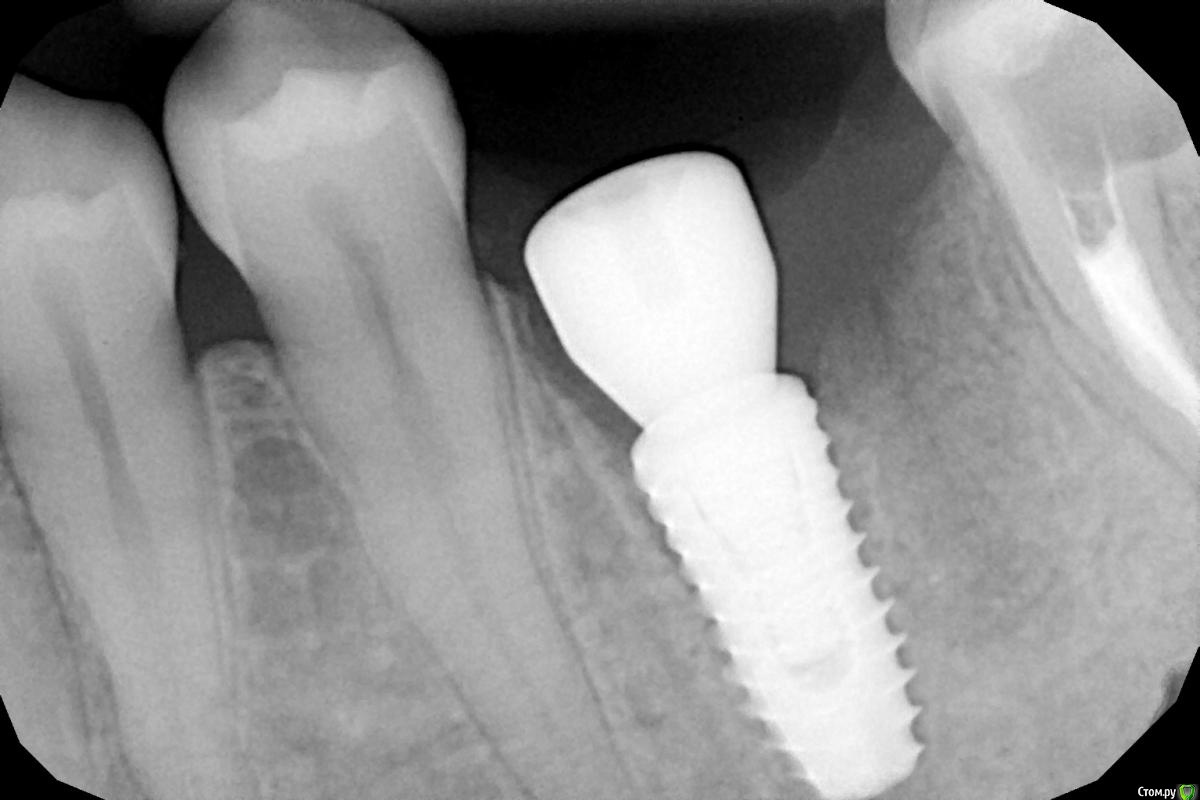

Женька Опубликовано 1 мая, 2021 Автор Поделиться Опубликовано 1 мая, 2021 Зафиксировали сегодня нашему технику циркон в полную анатомию... плюсом сажал сст одновременно и раздвинул десну язычно и вестибулярно. Зафиксировал без ишемии десны практически (немного побелела только). Что скажет по снимку, коллеги? 1 Ссылка на комментарий

Irouil Опубликовано 1 мая, 2021 Поделиться Опубликовано 1 мая, 2021 Какой техник технику коронку делал? Почему там зазор у основания?) Графтили под понтиком? Ссылка на комментарий

Женька Опубликовано 1 мая, 2021 Автор Поделиться Опубликовано 1 мая, 2021 (изменено) Техник сам себе коронку делал. Медиально зазор? Видимо потому, что при приклейке почему-то был люфт колпачка на абатменте... И мне этот момент непонятен, откуда этот люфт взялся. Под понтиком не графтил, там яма была вестибулярно в области понтика. Под понтиком полурасщепленный лоскут получился. И в этом месте циркон без глазури, только полировка. Щас модельку покажу. Изменено 1 мая, 2021 пользователем Женька Ссылка на комментарий

Aquarius Опубликовано 1 мая, 2021 Поделиться Опубликовано 1 мая, 2021 (изменено) Карен хорошо подметил про грешки. Это вообще что за прилегание? Абатмент пониже, фрезернуть и нормально выйти из десны, без балконов, вообще не вариант? Изменено 1 мая, 2021 пользователем Aquarius Ссылка на комментарий

Irouil Опубликовано 1 мая, 2021 Поделиться Опубликовано 1 мая, 2021 Ну пусть сам себе теперь работу переделывает))) ну правда, с таким высоким медиальным пиком этот навес - не комильфо А зачем Вы графтили вокруг винта на этапе сдачи постоянной работы? Ссылка на комментарий

Irouil Опубликовано 2 мая, 2021 Поделиться Опубликовано 2 мая, 2021 (изменено) 5 часов назад, Женька сказал: @Irouil потому что не додумался заграфтить на этапе установки... Всё настолько хреново? Теперь Ваш графт может непрогнозируемо повлиять на уровень зенита и глубину эпителиального прикрепления. При этом высота основания/циркона/глазури Вами уже выбрана и их соотношение с биологическими потом может не совпасть. насчет «хреново» - я уже написал про медиальную сторону, с такой близостью костной поверхности зазор может оказаться критичным. Вы просто покажите технику снимок и спросите - его самого устраивает всё? Изменено 2 мая, 2021 пользователем Irouil Ссылка на комментарий

Irouil Опубликовано 3 мая, 2021 Поделиться Опубликовано 3 мая, 2021 Ну тогда пусть носит) на мой взгляд на этом снимке все видно без каких-либо специальных обучений - должно быть гладко, а торчит юбка. Ссылка на комментарий